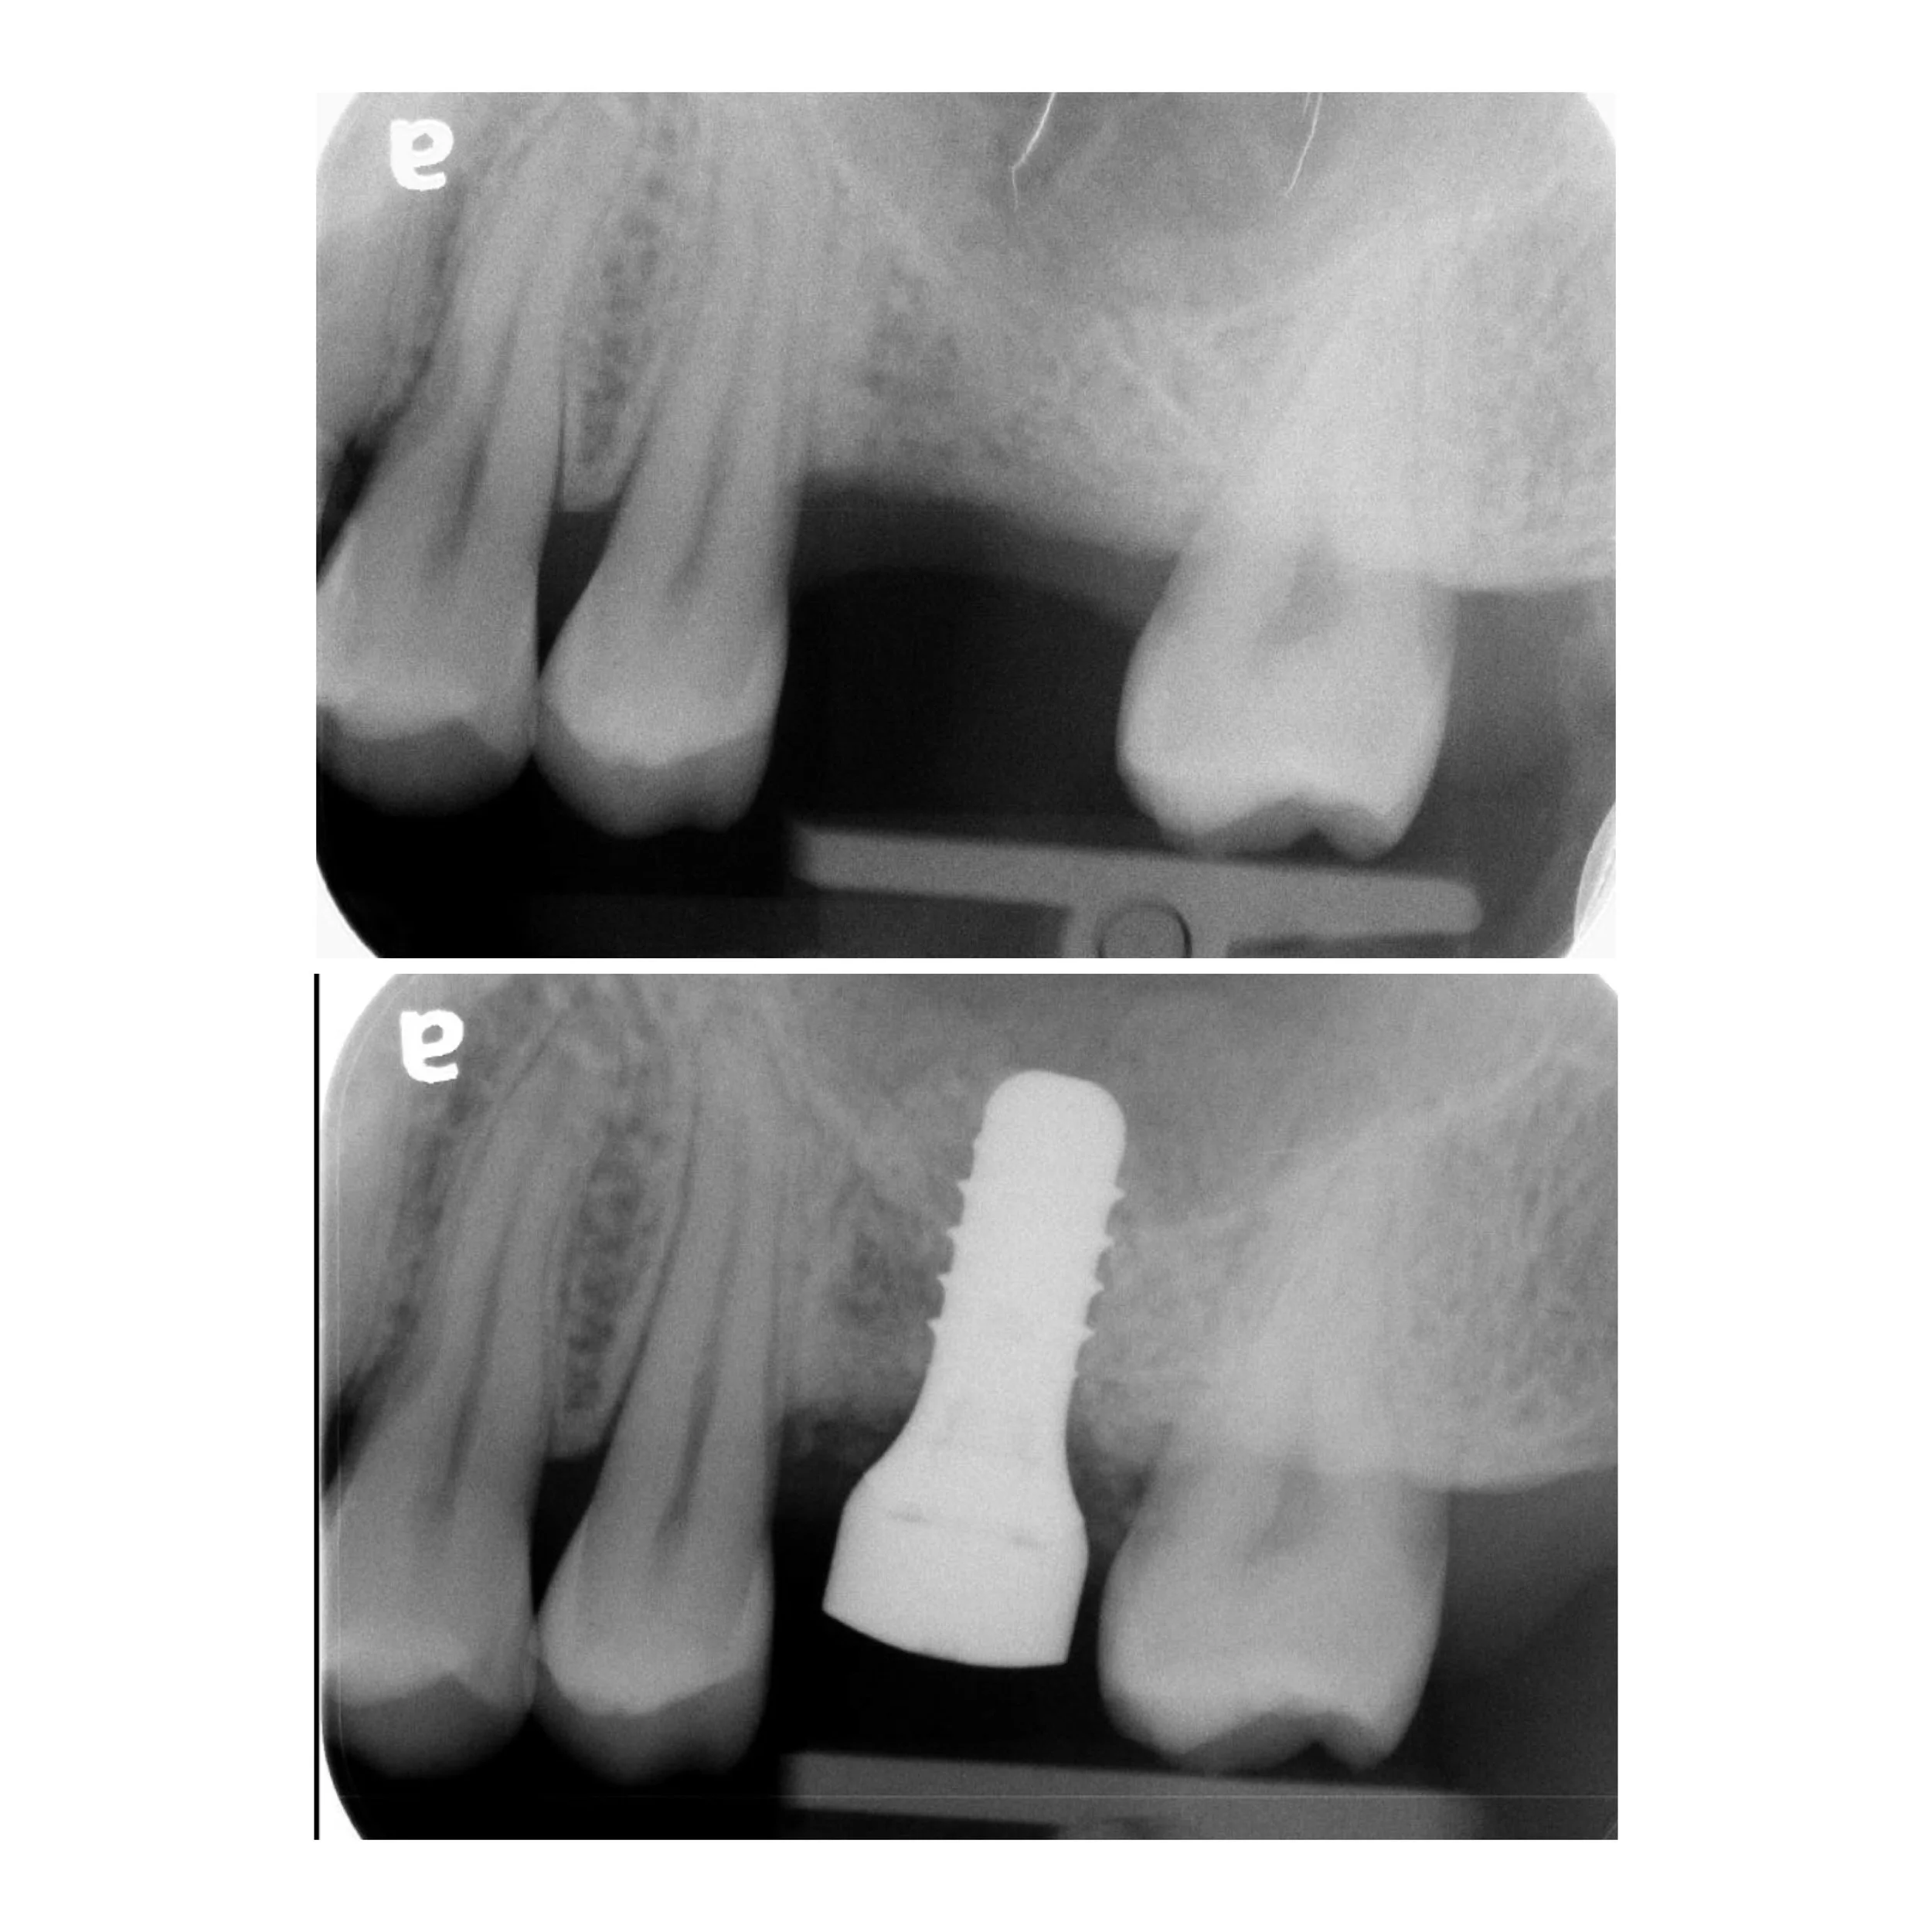

1. Single Tooth Restoration

The most common application for an implant is replacing a single missing tooth. Unlike a bridge, an implant does not require the "grinding down" of healthy adjacent teeth.

• The Component: A medical-grade titanium post acts as a synthetic root.

• The Benefit: It prevents the surrounding teeth from shifting and stimulates the jawbone to prevent bone loss.

• The Result: Once healed, your general dentist places a custom crown that looks, feels, and functions like a natural tooth.

1. 3D Imaging & Planning: We use CT scans to evaluate bone density and plan the exact placement of each implant.

3. Integration (Osseointegration): We allow a healing period for the bone to fuse with the implant.